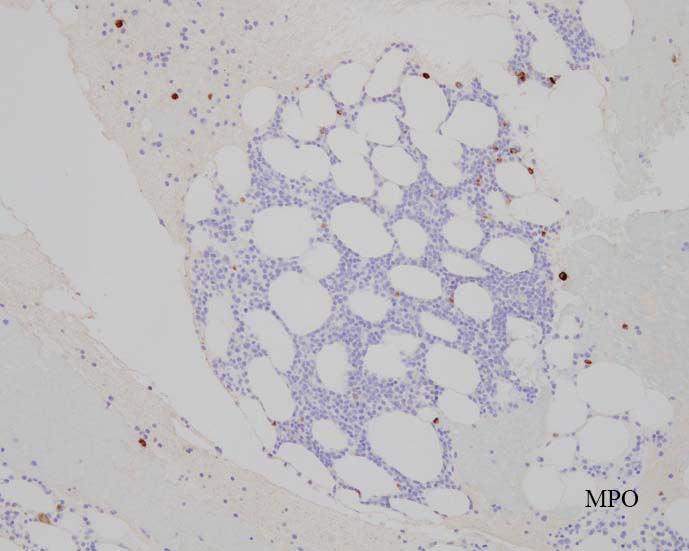

中型芽球様細胞増加 N/C=70-90%, 核は類縁液核網繊細 明瞭な核小体が 1-数個 細胞質は淡青色 MPO陰性.

N/C比 70-90%, 中型芽球様細胞が増加. 核は類縁液核網繊細, 明瞭な核小体が 1-数個 細胞質は淡青色 MPO陰性.

blastic cellsは, CD45+, CD34+, CD38+, TdT+, CD7+, HLA-DR+, CD123+. cCD3-, sCD3-(FCM), CD20-, CD19-とCD79a-(?) (plasma cellが陽性でIHCでは判定が難しい), MPO-.

CD3-, CD79aは増加しているplasma cellsが陽性で判定が難しい. CD10-, MPO-. (CD10は画像欠)